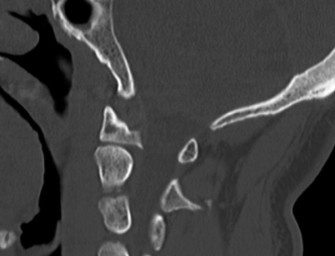

Recognize surgical and nonsurgical indications for a thoracic lymphoma? Definitively manage a thoracic lymphoma? CASE 13 A 23-year-old man was involved in a high-speed motor vehicle accident. On presentation to the trauma bay, his chief complaint was neck pain. Physical examination demonstrated that he was neurologically intact. Images of the cervical spine are shown in Figure 1–19A–B. Full workup demonstrated no other injuries.

Figure 1–19 A–B

The correct answer is (B). The imaging clearly demonstrates a Hangman’s fracture, also known as a C2 traumatic spondylolisthesis. The hallmark of this injury is a fracture through the pars interarticularis of C2, which effectively dissociates the anterior elements from the posterior arch and facet joints. A Jefferson fracture refers to C1 ring fractures that can have varying degrees of lateral displacement. There is no evidence of vertebral body comminution with posterior vertebral body involvement, which would be characteristic of a burst fracture. While some Hangman’s fractures can be associated with facet dislocation, there is no evidence of this on the imaging.

The correct answer is (B). Type I fractures have minimal horizontal displacement, no angulation, and the C2–3 disc remains intact. Type II fractures are both displaced and angulated, presumably hinging around the anterior longitudinal ligament. Importantly, these fractures reduce with longitudinal traction. Type IIA fractures have minimal horizontal displacement but are significantly angulated. It is presumed that the anterior fragment rotates in place, most likely disrupting the anterior longitudinal ligament. These injuries are worsened by traction and reduced with axial compression. Type III fractures have bilateral C2–3 facet dislocations.

The correct answer is (B). While type I fractures can be treated immediately in a hard collar, type II fractures are best treated initially with traction to achieve fracture reduction. After a short period of traction, the patient should be placed in a halo vest to allow mobilization. As indicated above, type IIA fractures should not be placed in traction; patients should be placed in a halo vest with some axial compression applied. Type III fractures require surgical reduction of the facet dislocation and internal stabilization. Objectives: Did you learn...? Identify a Hangman’s fracture based on imaging? Understand the classification of Hangman’s fractures?